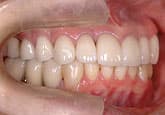

MJさん(20歳・女性)

初診時:左上の歯肉が痛い

初診時

3週間後

さらに正しいはみがき

を行って3週間後

ここまで患者さんが丁寧に歯をみがいただけです。

歯科医と衛生士は何もしていません。

さらに3週間後

歯石除去

歯石が見えてきたので、歯石を除去しました。

健康な歯肉に回復しました。